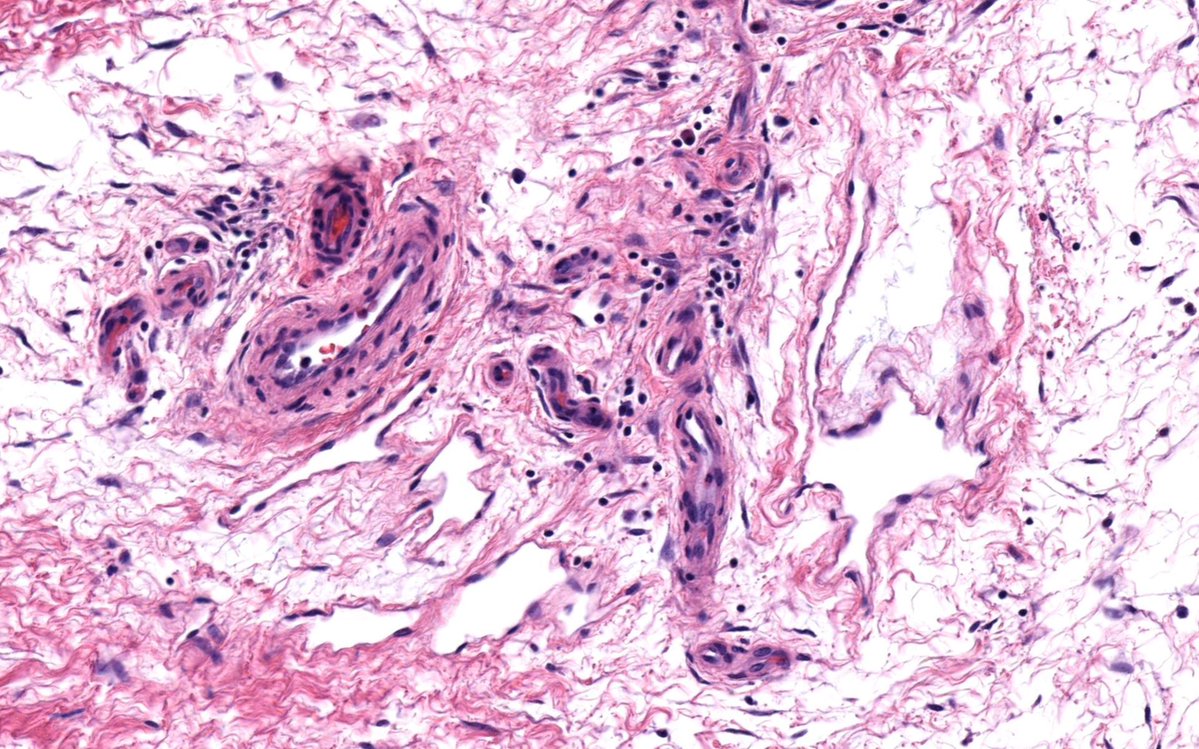

Does This Imaging Make Me Look NFATC2? The Value of... : The American Journal of Surgical Pathology journals.lww.com/ajsp/abstract/…

Does this imaging make me look NFATC2?